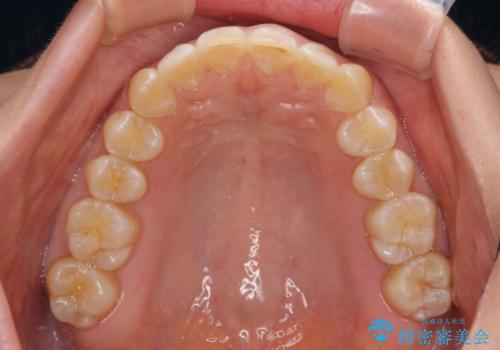

- 上顎前歯の前方に傾斜した咬み合わせを気にして来院された患者様です。

奥歯の咬み合わせを見ると、上顎が下顎に対して相対的に前方にありました。

深い咬み合わせを改善するためには、上顎臼歯を後方に移動させつつ、下顎の小臼歯を直立させる必要があります。

インビザライン単体で対応ることも検討できますが、達成する可能性が低いため、カリエールディスタライザーという補助装置を併用して、より確実性を上げることとしました。

奥歯の咬み合わせと深い咬み合わせを改善した後、インビザラインで歯列を整えることとしました。

カリエールディスタライザーや部分的なワイヤー矯正を併用したことで、確実かつ短期間で治療を終えることができました。